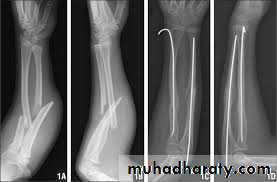

The key to successful treatment is to restore the length of the fractured ulna; only then can the dislocated joint be fully reduced and remain stable. In adults, this means an operation through a posterior approach. The ulnar fracture must be accurately reduced, with the bone restored to full length, and then fixed with a plate and screws.but in children closed reduction and plaster is usually satisfactoryChildren Rx Adult Rx